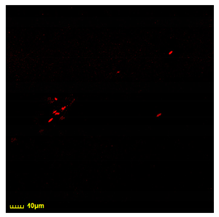

3.7.1. Comparison of the Phagocytosis for BALF Macrophages in Comparison with Model CD206+ Macrophages’ Cell Lines

3.7.2. Phagocytic Activity of CD206+ Macrophages from BALF Towards Different Strains of E. coli Cells

- The phagocytic ability (according to CLSM) of macrophages from the BALF against E. coli strains increases in the order of BL-21 ≈ W3110 < ATCC25922 << MH-1 ≈ JM109, which is correlated with the presence of pili and/or fimbriae in bacteria.